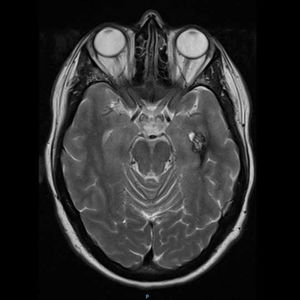

Additional TestsA genetic study revealed a heterozygous pathogenic variant of the KRIT1 gene in the patient and 4 of his children. Magnetic resonance imaging (MRI) showed cerebral venous malformations in one of the patient’s daughters (Fig. 3). None of the remaining family members who carried the mutation showed any vascular alterations of the central nervous system (CNS).

Screening for nervous system involvement is performed using gradient echo MRI. MRI reveals a characteristic popcorn-like appearance, consisting of a well-delimited reticulated nucleus, heterogeneous signal due to bleeding at different stages, and a hypointense hemosiderin ring.4 To date, surgery is the only described treatment, and is indicated for single, symptomatic lesions in specific locations, but not for multiple or asymptomatic lesions, with certain exceptions.4 Long-term use of statins is being studied in a clinical trial, for which data are not yet available.4